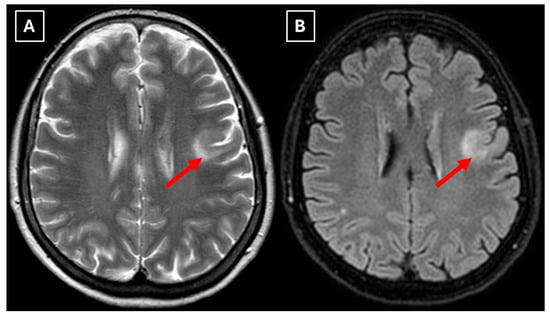

Two months later a follow-up head MRI was performed. It showed a substantial decrease in the volume of the lesion, no mass effect on the surrounding structures, and no perifocal edema (Figure 6 and Figure 7). No other demyelinating lesions were found in the cervical and thoracic spine MRI. The multiple sclerosis board recommended an MRI follow-up after six months as well as a clinical evaluation of the patient.

Figure 6. The 2-month follow-up MRI scan of the brain. In both (A): axial T2W axial sequence and (B): axial FLAIR, the mass has drastically decreased in size and has almost disappeared. A hyperintense demyelination focus can be seen subcortically in the basal parts of the left frontal lobe, which extends more into the white matter and has no mass effect on the surrounding structures. Red arrow—tumefactive demyelinating lesion.

Figure 7. The 2-month follow-up MRI axial scan of the brain. Previously seen peripheral rim-like diffusion restriction is resolved and there is residual minimal vasogenic edema on the axial trace image (A). (B): ADC map. (C): SWI sequence shows no evidence of a left frontal lobe mass but a prominent central traversing vein in the lesion site. (D): T1 postcontrast sequence shows minimal patchy contrast enhancement along the margin of the lesion. Based on the observed changes over the past 2 months, it is most likely that the findings correspond to a demyelinating lesion. Red arrow—tumefactive demyelinating lesion.

Finally, we provide a high-resolution MRI follow-up of two months’ duration showing near-complete regression of the lesion after corticosteroid therapy. The lesion decreased from 37.34 mm × 34.85 mm (AP × LL) to 24.87 mm × 29.71 mm following two weeks of corticosteroid therapy and after almost two months from the first MRI scan to minimal patchy contrast enhancement (Figure 7D). This marked decrease in the size of the lesion gives strong evidence that a demyelinating rather than neoplastic process is present.

Follow-up MRI showed lesion shrinkage after two weeks (Figure 4) and by two months, near-complete lesion regression and resolution of perifocal edema. The radiological course was typical for TDLs and no alternative differential diagnosis appeared reasonable, as both the clinical response to therapy and MRI follow-up strongly supported the demyelinating origin. Thus, biopsy was not performed in this case. In the literature similar cases have been reported where biopsy was avoided, as the disease responded to treatment and imaging findings were consistent with a demyelinating process [27]. Moreover, biopsy of the brain in TDLs carries considerable procedural risks, including seizures and post-operative infections [2]. However, despite the lesion regression after corticosteroid therapy, which was supportive of a TDL diagnosis, the lack of biopsy confirmation represents a limitation in this case and warrants explicit acknowledgment of the risk of misdiagnosis, especially with lesions that have less certain regression.